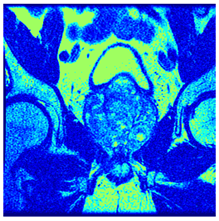

| Image | nt = 3 | nt = 4 | nt = 5 | nt = 8 |

|---|---|---|---|---|

| 1 | ![]() | ![]() | ![]() | ![]() |

| 2 | ![]() | ![]() | ![]() | ![]() |

| 3 | ![]() | ![]() | ![]() | ![]() |

| 4 | ![]() | ![]() | ![]() | ![]() |

| 5 | ![]() | ![]() | ![]() | ![]() |

| 6 | ![]() | ![]() | ![]() | ![]() |

| 7 | ![]() | ![]() | ![]() | ![]() |

| 8 | ![]() | ![]() | ![]() | ![]() |

| 9 | ![]() | ![]() | ![]() | ![]() |

| 10 | ![]() | ![]() | ![]() | ![]() |

| 11 | ![]() | ![]() | ![]() | ![]() |